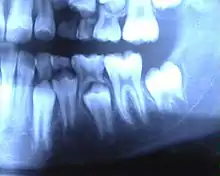

L'humain possède 20 dents de lait : 8 incisives, 4 canines et 8 molaires.

Le début de la calcification (début de la formation) se fait au 5e ou 6e mois de grossesse pour toutes les dents de lait. La première dent apparaît en bouche vers le sixième mois après la naissance ; mais elle peut être présente dès la naissance. Parfois une telle dent présente à la naissance est en fait une dent supplémentaire, qui va tomber rapidement. La première perte de dent de lait survient vers six ans.

- Incisives centrales : éruption à 6-10 mois / chute à 6-8 ans

- Incisives latérales : éruption à 8-12 mois / chute à 7-9 ans

- Canines : éruption à 18-24 mois / chute à 9-12 ans

- Première molaire : éruption à 12-18 mois / chute à 9-11 ans

- Deuxième molaire : éruption à 24-30 mois / chute à 10-12 ans

- Couronne : teinte plus claire ; cuspides plus pointues, dents plus globuleuses, rétrécissement cervical (collet) moins marqué.

- Racines : plus fines et plus divergentes, pour laisser la place au germe sous-jacent de la dent permanente.